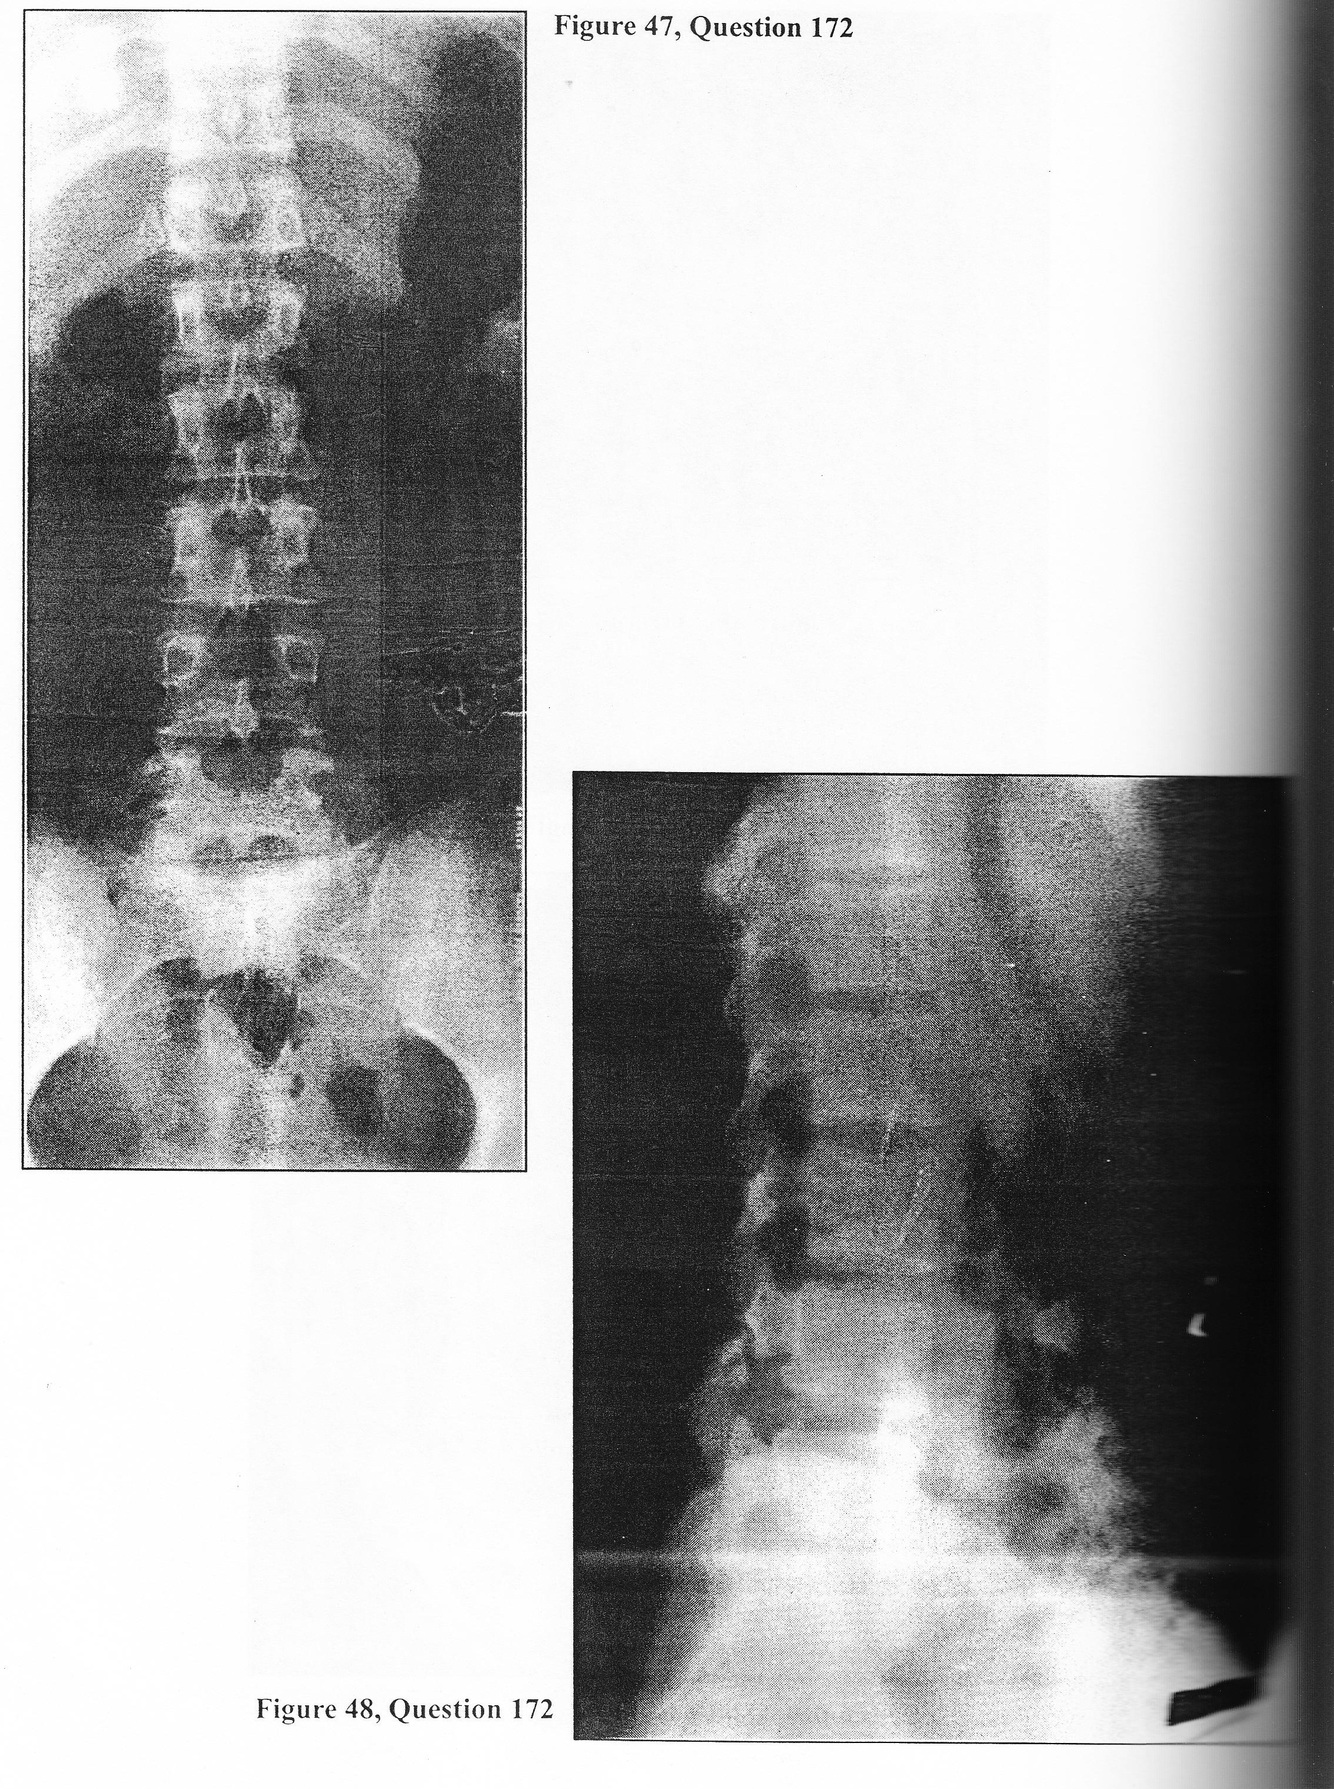

A 26-year-old male presents complaining of a two-year history of gradually progressive low back pain. It has been intermittent in nature, aggravated by physical activity, and relieved by rest. His most recent exacerbation occurred one month ago during a triathalon. The pain remains localized to the low back region with radiation into both buttocks but not the legs. He can no longer participate in his usual sports because of discomfort. Physical examination reveals the young man to be neurologically intact. Straight- leg raising and femoral stretch testing are normal. There is no clinical evidence of kyphoscoliosis. There is no joint tenderness. Range of motion of the lumbar region is normal. Plain x-rays accompany the patient (Figures 47 and 48). 172. At this point you WOULD:

A. prescribe anti-inflammatory and analgesic medications, reduced activity, and external bracing

B. obtain a lumbar MRI

C. place the patient on bed rest with bathroom privileges for three weeks

D. order a thoracolumbar spinal orthosis with a hip spica

E. all of the above

A 26-year-old male presents complaining of a two-year history of gradually progressive low back pain. It has been intermittent in nature, aggravated by physical activity, and relieved by rest. His most recent exacerbation occurred one month ago during a triathalon. The pain remains localized to the low back region with radiation into both buttocks but not the legs. He can no longer participate in his usual sports because of discomfort. Physical examination reveals the young man to be neurologically intact. Straight- leg raising and femoral stretch testing are normal. There is no clinical evidence of kyphoscoliosis. There is no joint tenderness. Range of motion of the lumbar region is normal. Plain x-rays accompany the patient (Figures 47 and 48).

A. flexion and extension lateral lumbar radiographs

B. obtain tomograms of the lumbar spine

C. perform a bone scan

D. draw blood cultures and an erythrocyte sedimentation rate

E. lumbar puncture

A. hereditary

B. traumatic

C. degenerative

D. none of the above